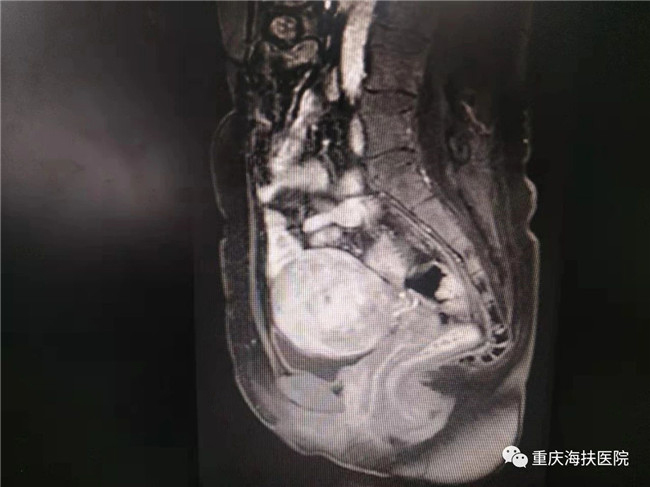

2019年9月18日,39歲的李女士在重慶海扶醫(yī)院微信群里向其主治醫(yī)師楚麗報喜:剖宮產(chǎn)一個6.2斤的海扶小公主!

2017年10月,李女士因子宮腺肌病到重慶海扶醫(yī)院就診,那時的她已經(jīng)被痛經(jīng)折磨了4年,疼痛評分(VAS)高達7-8分,嚴(yán)重影響正常生活、工作甚至睡眠,多地醫(yī)院建議切除子宮。

李女士因為有保留子宮和再生育的愿望,毅然選擇了不開刀、不流血的聚焦超聲消融手術(shù),術(shù)中消融病灶達6公分,消融效果良好。術(shù)后李女士發(fā)現(xiàn)自己的痛經(jīng)癥狀明顯緩解,并在1年后成功妊娠,于2019年9月18日剖宮產(chǎn)一個6.2斤的海扶小公主!